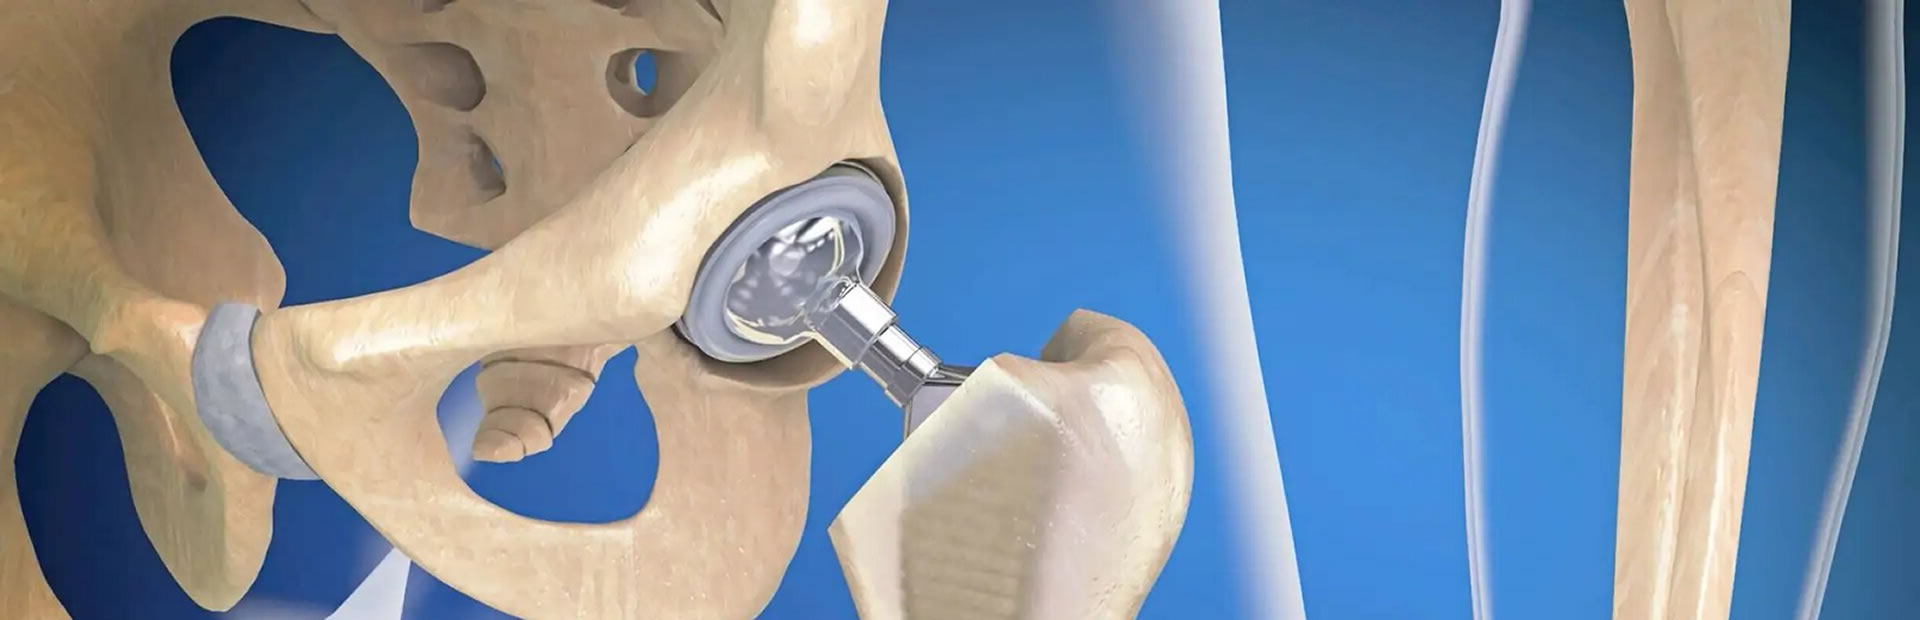

PRÓTESIS ARTICULARES